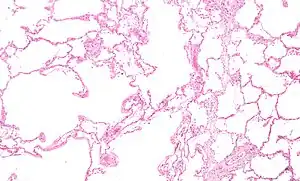

A severe case of bullous emphysema -

Axial CT image of the lung of a person with end-stage bullous emphysema -